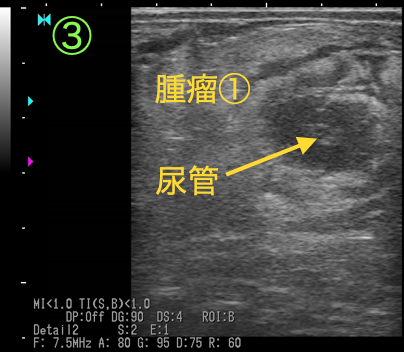

断面③④

腫瘤①に巻き込まれた尿管は、断面②と比較すると押しつぶされるようにして狭窄しています。

以上の画像と触診から、腫瘤①が尿管を巻き込むように形成されており、巻き込まれた尿管は著しく狭窄し(③④)、腎盂および腫瘤より腎臓側の尿管は鬱滞した尿により著しく拡張している(①②)ことがわかりました。